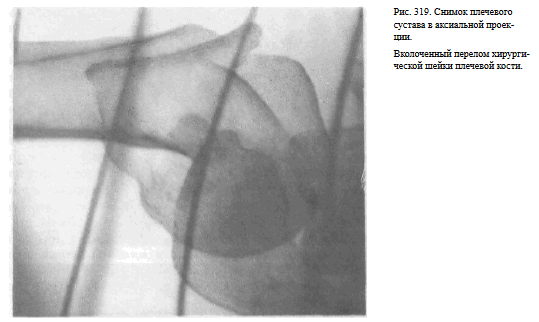

Информативности снимка. На снимке видны головка плечевой кости, края суставной впадины лопатки, плечевой и клювовидный отростки.

Краеобразующими являются малый бугорок плечевой кости, передняя поверхность диафиза плеча по верхнему контуру и задняя поверхность диафиза плеча по нижнему контуру (рис.318, 319).